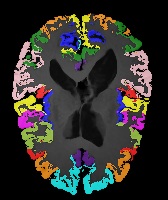

Moving Target Mono-0 Mono-5 DA-1 DA-5 Mono-200 Refer to caption Refer to caption Refer to caption Refer to caption Refer to caption Refer to caption Refer to caption Refer to caption Refer to caption Refer to caption Refer to caption Refer to caption Refer to caption Refer to caption

Image Manual Seg DA-1 Mono-21 DA-21 Mono-65 Refer to caption Refer to caption Refer to caption Refer to caption Refer to caption Refer to caption

Figure 2:  Examples of knee MRI registration (top) and brain MRI segmentation (bottom) results. Top: The first two columns are the moving image/segmentation and the target image/segmentation followed by the warped moving images (with deformation grids)/segmentations by different models. Bottom left to right: original image, manual segmentation, and predictions of various models. Mono-i𝑖i and DA-i𝑖i represent the mono- and DA models with i𝑖i manual segmentations respectively.

Results: All trained networks are evaluated using Dice overlap scores between predictions and the manual segmentations for the segmentation network, or between the warped moving segmentations and the target segmentations for the registration network. Tabs. 1 and 2 show results for the knee and brain MRI experiments respectively in Dice scores (%). Fig. 2 shows examples of knee MRI registrations and brain MRI segmentations.

Qualitative results: DA achieves more anatomically consistent registrations than the mono-networks on the knee (Fig. 2) and Brain MRI samples (see supplementary material).